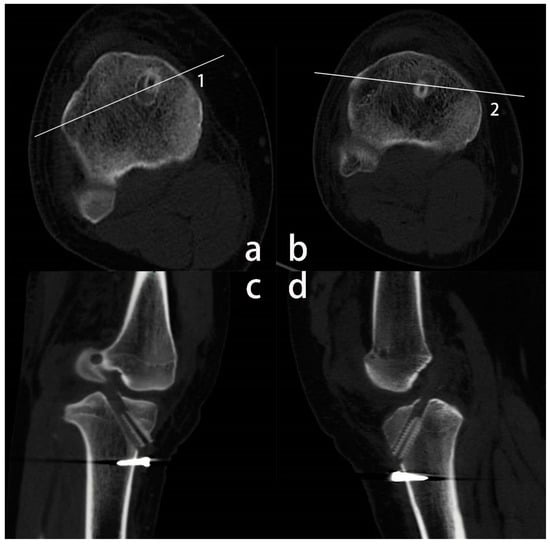

2.4. Imaging Evaluations